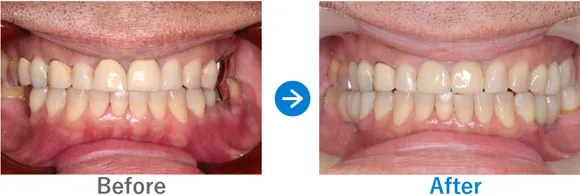

ほぼ虫歯な状態から、できるだけ歯を残した最小限のインプラントできれいな口元に

全顎ランパントカリエス(複数の歯に同時に虫歯が発生する状態)

インプラント4本:上顎2本、下顎2本、残せる歯はすべて補綴治療

4,917,000円(内訳:抜歯テルプラグ、GBR、根管治療、インプラント4本(ストローマン)、ガイド、全顎仮歯、補綴治療、セデーション、保証20年)

来院の背景

歯医者が苦手で、子供時代に歯科にかかったきりでした。ほとんどの歯に虫歯がある状態だったため、心配になったお父様が連れてこられました。

治療結果

まだお若いため、残せる歯はできるだけ残したうえで補綴治療(クラウンやブリッジなどによる治療)を行い、どうしても抜歯が必要な歯4本のみインプラントを行う方針で治療を進めました。

治療後は、見た目が整ったことはもちろん、しっかり噛めるようになったと喜んでいらっしゃいました。歯磨きが苦手とのことなので、定期メンテナンスでのアフターフォローも大切です。